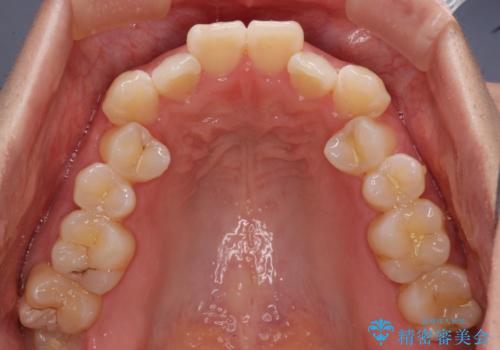

- 口元の突出感と口の閉じにくさ、前歯のデコボコを気にして来院された患者様です。

上下左右第一小臼歯4本を抜歯し、ワイヤー装置にて口元を引っ込めるよう矯正治療を行うこととしました。

骨格的に下顎骨が前方位にあるため、口元の突出感改善には限界があると思われましたが、唇の閉じにくさが改善するほど引っ込めることができました。